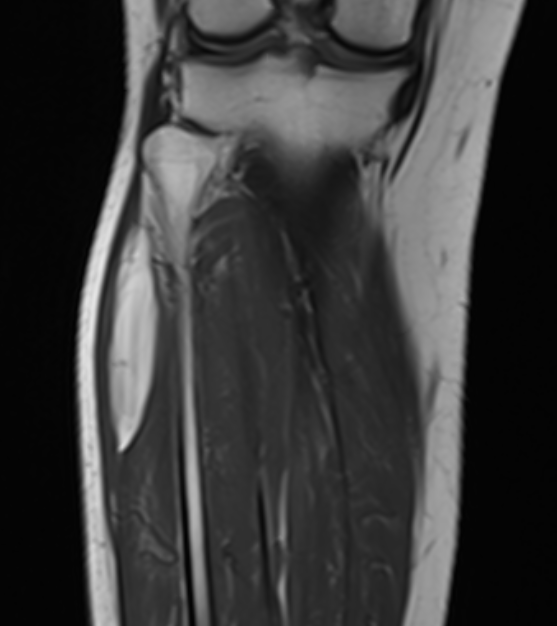

Lipoma

Lipoma 1Lipoma 2

Lipoma tibia

Lipoma 1Lipoma 2Lipoma 3

Lipoma shoulder - superficial to fascia